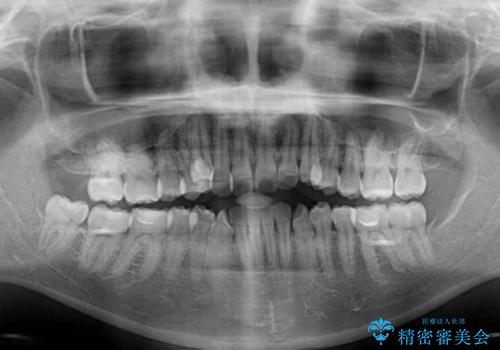

- 八重歯と上下前歯のでこぼこを気にして来院された患者様です。

上下前歯部叢生のスペース獲得のため、上下顎左右小臼歯各1歯(計4本)と全ての親知らずを抜歯して、矯正治療を行うこととしました。